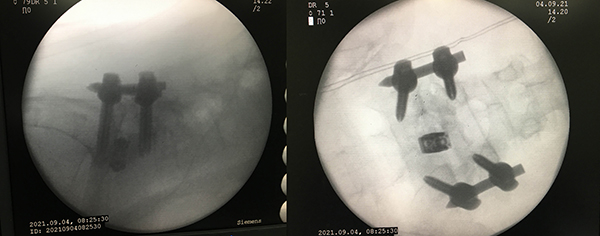

手術(shù)很順利,脊柱外科在微創(chuàng)置釘技術(shù)下將滑脫完全復(fù)位,術(shù)后覃阿姨腰痛逐漸緩解,她對治療效果非常滿意,現(xiàn)已康復(fù)出院。

術(shù)后影像